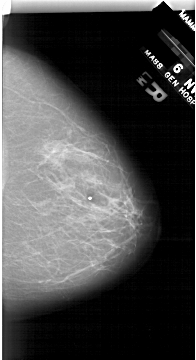

A_1687_1.RIGHT_CC

RIGHT_CC LINES 6466 PIXELS_PER_LINE 3511 BITS_PER_PIXEL 12 RESOLUTION 43.5 NON_OVERLAY

FILE: A_1687_1.LEFT_CC.OVERLAY

TOTAL_ABNORMALITIES 1

ABNORMALITY 1

LESION_TYPE MASS SHAPE LOBULATED MARGINS ILL_DEFINED

ASSESSMENT 4

SUBTLETY 4

PATHOLOGY BENIGN

TOTAL_OUTLINES 1

BOUNDARY